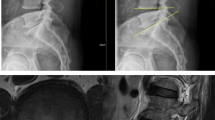

Based on computed tomography (CT) images, facet joint arthropathy of the lumbar spine was graded using a 4-grade scale as proposed by Weishaupt et al.22 Weishaupt’s classification of facet joint degeneration has been extensively used23,24. Two orthopaedic spine surgeons (P–H. C. and Y-C. Y. with 10-year and 5-years clinical experiences, respectively), who were not involved in the surgical treatment of included patients, graded the severity of facet joint arthropathy independently; disagreements over grading were resolved by consensus. Example CT images for 4 grades of facet joint arthropathy are shown in Fig. 1. We examined 5 facet joint levels, including L1-L2, L2-L3, L3-L4, L4-L5, and L5-S1. Since each level has 2 sides (right and left), each patient had 10 numerical grades of facet joint arthropathy.